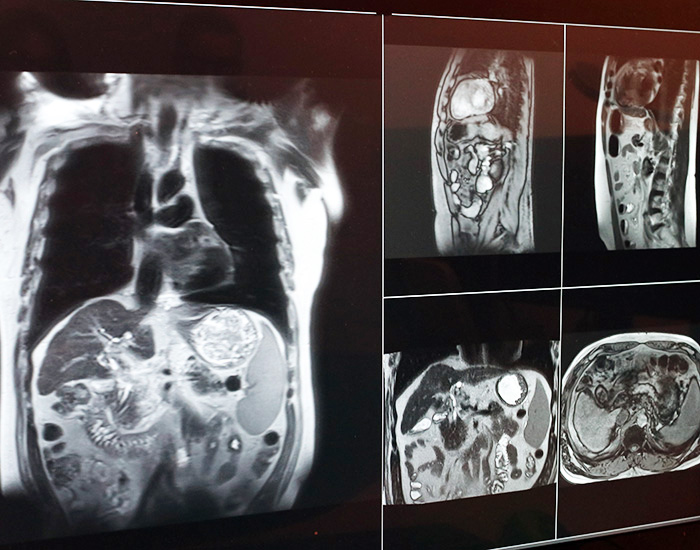

radiation image 700 brite

Image taken on

Apr 15, 2026, 15:27 by Tonia Twichell